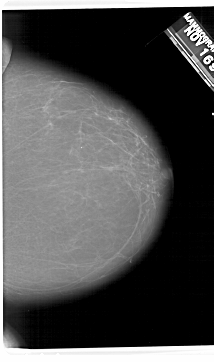

A_1406_1.RIGHT_MLO

RIGHT_MLO LINES 5671 PIXELS_PER_LINE 3616 BITS_PER_PIXEL 12 RESOLUTION 43.5 NON_OVERLAY